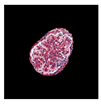

| True label: FSGS |  |  |  |  |  |

| single-multiclass: FSGS p = 0.964, IoU = 0.063 | |||||

| multiple-binary: FSGS p = 0.999, IoU = 0.076 | |||||

| spatially guided: FSGS p = 0.862, IoU = 0.390 | |||||